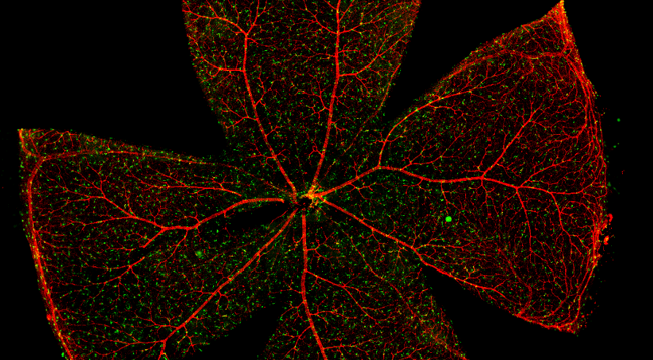

视网膜血管作为人体内唯一可以进行非创伤直接观察的深层微血管,其生理状况的检查对高血压、糖尿病、动脉硬化等心血管疾病的诊断、治疗评价具有重要意义。

一般而言,眼底图像通常都是通过激光扫描成像进行采集,但是由于眼底可观测的视野往往是很有限的,一个患者的眼底信息需要多张扫描图像才能完全显示出来。这种局限性大大不利于病情进行全面的、细致的诊断。Tissue Cytometry全景组织流式定量分析技术进行全景图像获取,在单细胞、组织结构、细胞空间信息等多个层面进行定位、定性、定量分析。从而更好的对病变区域进行有针对性的跟踪观察和全面分析。

视网膜荧光样本中小胶质细胞胞体、神经纤维识别、血管识别、血管斑点识别、神经元与血管的距离分析。

1. 利用TissueFAXS系统进行玻片荧光的全景扫描。

2. 使用StrataQuest分析软件进行定量分析。